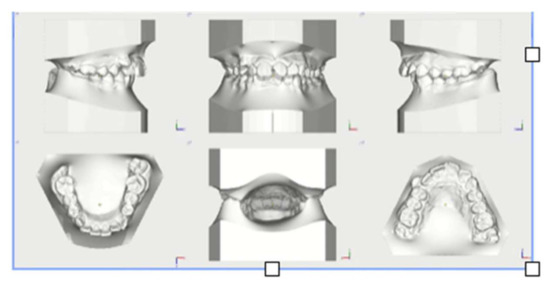

Figure 8.

Post-treatment models.

Treatment lasted 26 months. Treatment goals were reached: correction of class II malocclusion was obtained, bilateral molar and canine class I occlusion was achieved, anterior crowding and deep bite were corrected and the smile’s aesthetic was improved.

Once sagittal discrepancy was solved, after 9 months, treatment continued with a fixed multi-brackets therapy in upper and lower arches with a Bidimensional Technique. Multibrackets treatment objectives were alignment, levelling and occlusion finishing. Intermaxillary elastics were used to complete class II correction to obtain occlusion finishing.

At the end of therapy, a fixed retention was applied to both arches with the addition of an Essix for the upper arch.